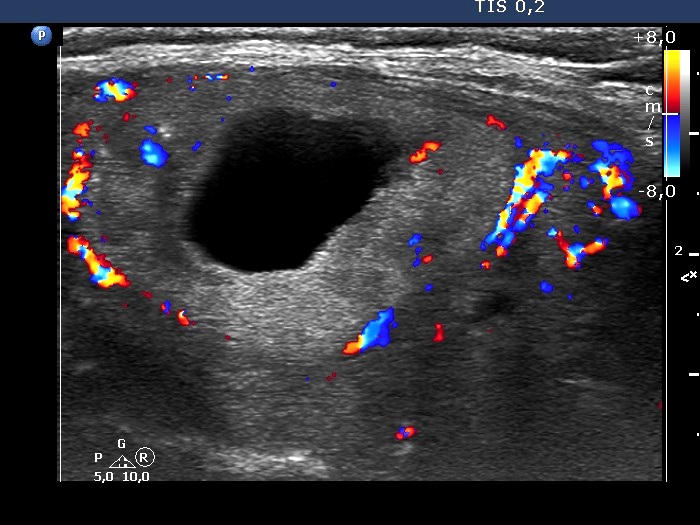

The composition of the nodule - case 1530 (ultrasonographic picture 4)

Right lobe, longitudinal scan

Right lobe, longitudinal scan, color Doppler mode.